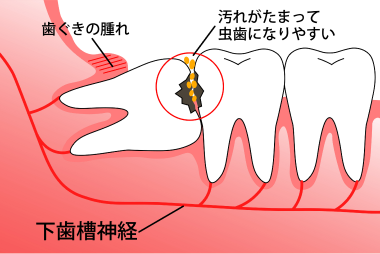

親知らずについて

親知らずは「第三(だいさん)大臼歯(だいきゅうし)」「智歯(ちし)」とも呼びます

最後に生えてくる奥歯で狭い場所に生えるためほとんどが斜めや真横に生えてきます。同様の状態で歯茎の中にあり表面に出てこない場合(埋伏智歯・水平埋伏智歯)も多くあります。

1. 智歯周囲炎の場合

智歯周囲炎とは

唾液中の細菌に親知らずの周辺が感染して起こる炎症のことです。主に以下の症状があります。

- 歯茎の腫れ・出血や膿が出る

- 触れると痛みがある

- 顎のリンパ節の腫れ(顔が腫れる)

- 口が開きにくい(開口障害)

- 痛み止めが効きにくい など

体調不良や疲労、免疫力が低下しているときに症状が現れることが多くあります。

2. 虫歯や歯周病がある場合

親知らずはお口の中の一番奥に生えているため歯磨きが難しく、虫歯や歯周病になりやすい歯です。

親知らずの前の歯も虫歯や歯周病になり易くなります。

図のように下歯槽神経に歯がかかっている方

麻痺やしびれが出る可能性があります。